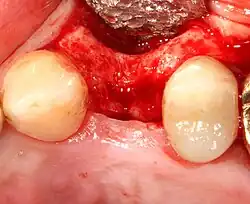

Placing the implant

Most implant systems have five basic steps for placement of each implant:[28]: 214–221

- Soft tissue reflection: An incision is made over the crest of bone, splitting the thicker attached gingiva roughly in half so that the final implant will have a thick band of tissue around it. The edges of tissue, each referred to as a flap, are pushed back to expose the bone. Flapless surgery is an alternate technique, where a small punch of tissue (the diameter of the implant) is removed for implant placement rather than raising flaps.

- Tissue adaptation: The gingiva is adapted around the entire implant to provide a thick band of healthy tissue around the healing abutment. In contrast, an implant can be "buried", where the top of the implant is sealed with a cover screw and the tissue is closed to completely cover it. A second procedure would then be required to uncover the implant at a later date.

An increasingly common strategy to preserve bone and reduce treatment times includes the placement of a dental implant into a recent extraction site. On the one hand, it shortens treatment time and can improve aesthetics because the soft tissue envelope is preserved. On the other hand, implants may have a slightly higher rate of initial failure. Conclusions on this topic are difficult to draw, however, because few studies have compared immediate and delayed implants in a scientifically rigorous manner.[55]